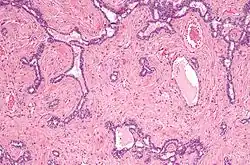

Micrograph of the rete testis involved by seminoma. H&E stain.